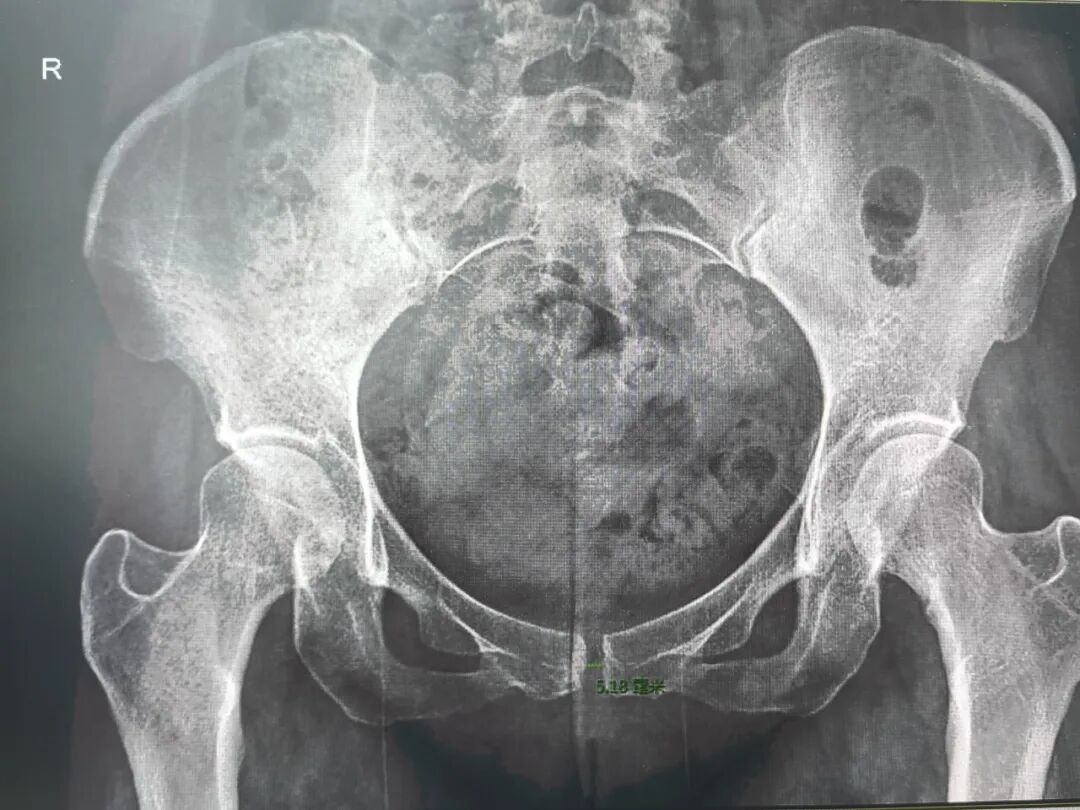

产后正常骨盆片子,图源:科室供图

我们的骨盆是一个环形的骨性结构,它只有两个间隙:一个是耻骨联合,其正常间隙只有0.5cm,且有软骨填充;另一个是骶髂关节,间隙就更小了,几平可以忽略不计。这样的骨性结构是无法徒手进行缩小的。

孕期为了适应分娩,身体会分泌松弛素,让韧带变得松弛,分娩时耻骨联合会轻微分离,这是生理性的变化。

分娩后,随着激素水平回落,这些关节和韧带会逐渐恢复,这个过程通常需要42天-3个月左右。